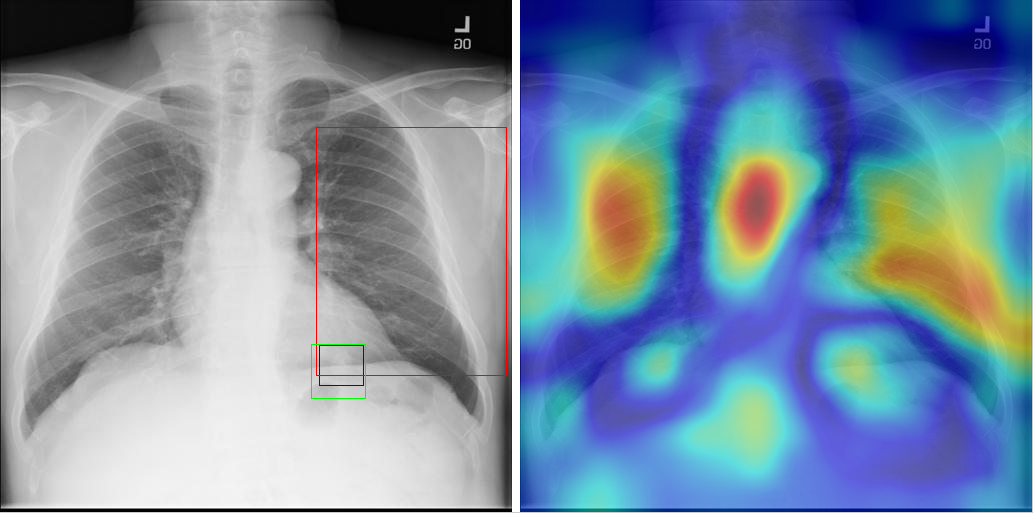

Table 8 to Table 15 illustrate localization results from each of 8 disease classes together with associated report and mined disease keywords. The heatmaps overlay on the original images are shown on the right. Correct bounding boxes (in green), false positives (in red) and the groundtruth (in blue) are plotted over the original image on the left.

In order to quantitatively demonstrate how informative those heatmaps are, a simple two-level thresholding based bounding box generator is adopted here to catch the peaks in the heatmap and later generated bounding boxes can be evaluated against the ground truth. Each heatmap will approximately results in 1-3 bounding boxes. We believe the localization accuracy and AFP (shown in Table 7) could be further optimized by adopting a more sophisticated bounding box generation method, e.g. selective search [47] or Edgebox [18]. Nevertheless, we reserve the effort to do so, since our main goal is not to compute the exact spatial location of disease patterns but just to obtain some instructive location information for future applications, e.g. automated radiological report generation. Take the case shown in Table 8 for an example. The peak at the lower part of the left lung region indicates the presence of “atelectasis”, which confer the statement of “…stable abnormal study including left basilar infilrate/atelectasis, …” presented in the impression section of the associated radiological report. By combining with other information, e.g. a lung region mask, the heatmap itself is already more informative than just the presence indication of certain disease in an image as introduced in the previous works, e.g. [42].

Radiology report Keyword Localization Result

findings: unchanged left lower lung field infiltrate/air bronchograms. unchanged right perihilar infiltrate with obscuration of the right heart border. no evidence of new infiltrate. no evidence of pneumothorax the cardiac and mediastinal contours are stable. impression: 1. no evidence pneumothorax. 2. unchanged left lower lobe and left lingular consolidation/bronchiectasis. 3. unchanged right middle lobe infiltrate Pneumonia; Infiltration [Uncaptioned image]

Table 14: A sample of chest x-ray radiology report, mined disease keywords and localization result from the “Pneumonia” Class. Correct bounding box (in green), false positives (in red) and the ground truth (in blue) are plotted over the original image.